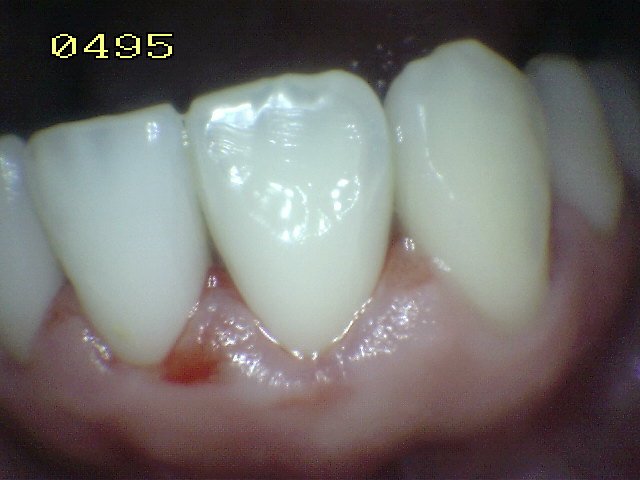

Casos clínicos de

fluorosis leve. |

Se caracteriza por esmalte normal,

liso, traslucido y cristalino de color uniforme.

Estas características permanecen aún después

del secado con aire prolongado |